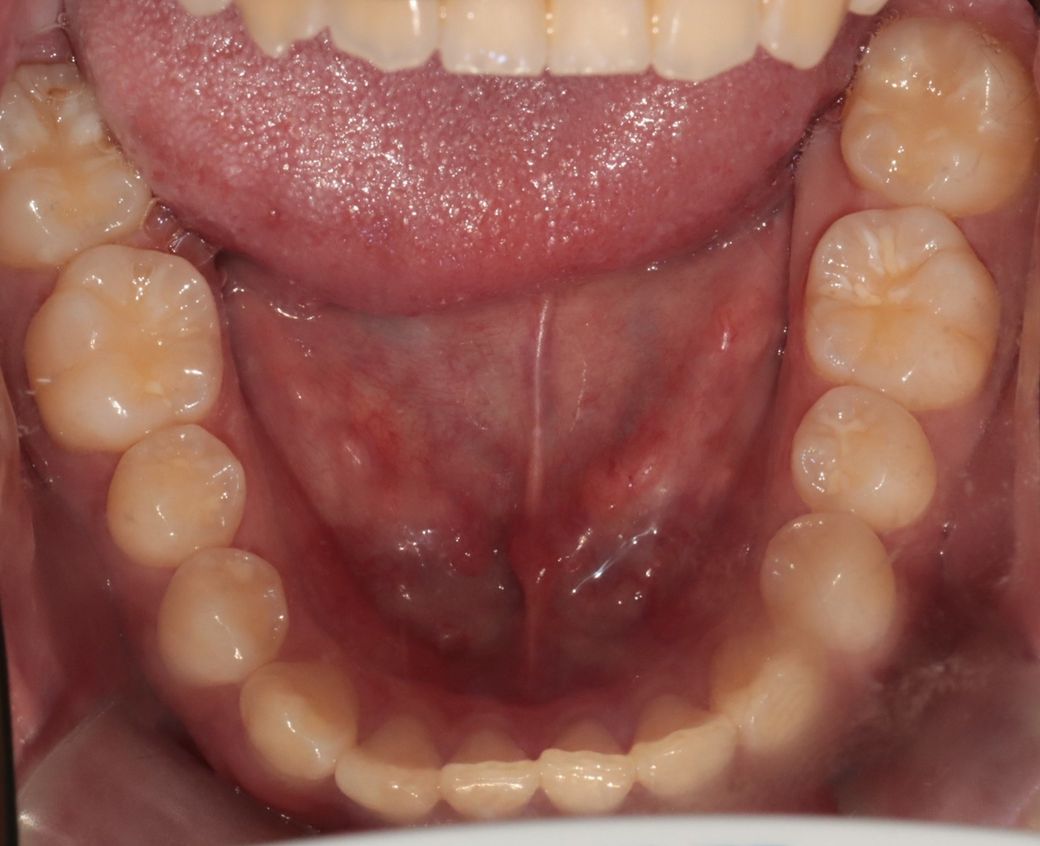

A치과) 상악에 비해 하악이 긴편이나 정상범위라고 볼수 있어 주걱턱은 아니라고 봅니다. 그래서 수술적 치료는 필요치 않아 보입니다. 치아상태는 전치부 총생 및 전방경사가 있고 상악 우측절치 반대교합이 있다 장기적으로는 좋지못하다. 앞니 부분교정 또는 인비절추천